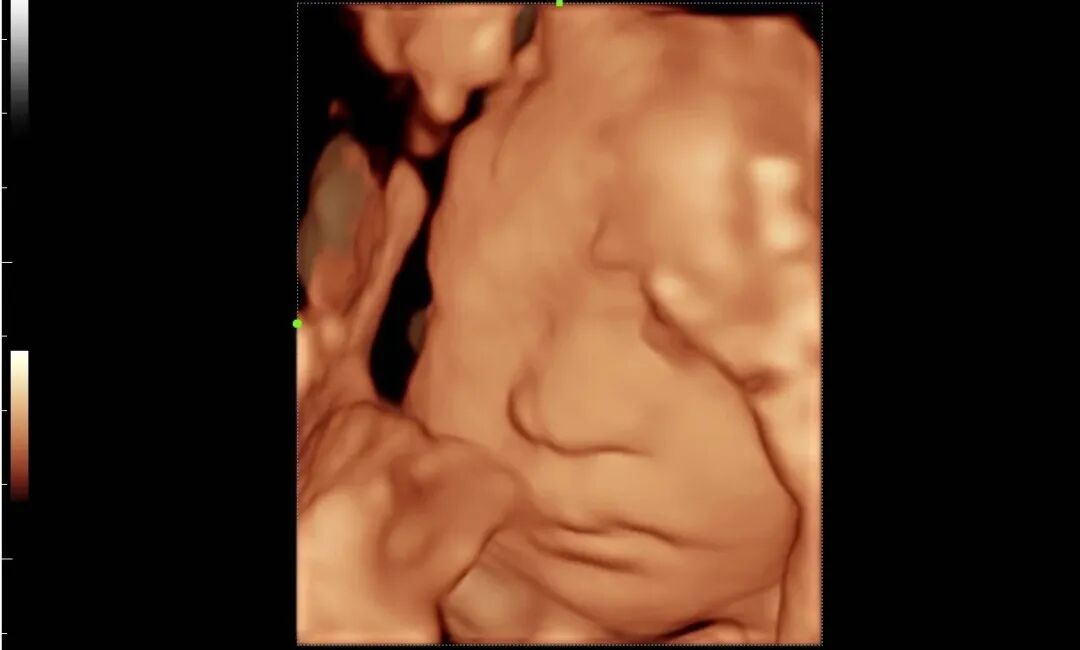

为进一步提高我院诊疗检查与诊断水平,不断满足城乡患者日益增长的就医需求,健全和完善医疗保障体系。2022年12月我院引进了mindray- Resonal9T高端彩色多普勒超声系统正式投入使用,此设备具备超声介入、超声造影、超声高帧率 STE 剪切波弹性成像及应变式弹性成像(甲状腺、乳腺、肝脏),二维、三维、四维、阴式、盆底、心脏及血管超声等功能。此设备的引进标志着海伦影像学科将跨越新的高度,以此助力城乡百姓解决看病难,看病贵的就医难题!